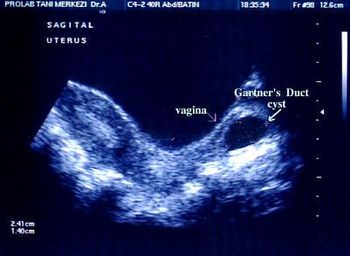

This random retrospective cross-sectional study was preformed to determine the frequency of uterine malformation in restricted gene pool communities. In 4 groups of women desiring to conceive during their reproductive years, all women lives in lacrete, a community in north Alberta, Canada